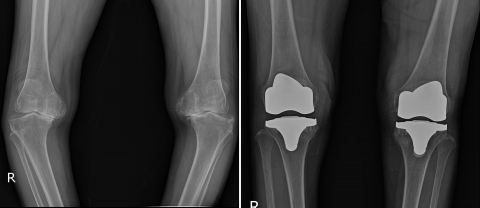

‘인공관절 치환술’은 무릎의 연골이 모두 닿고 마모된 경우 권유되는 수술이다. 치환술은 심하게 닳은 관절의 전부를 제거해 내고 인체친화적인 재료로 만들어진 특수 금속과 플라스틱 재질로 된 인공관절을 삽입한다.

이 치환술을 받게 되면 대부분의 환자는 관절염으로 인한 통증을 크게 줄일 수 있고, 오자형의 다리, 휘어진 다리가 반듯하게 펴지고 활동량이 증가하면서 노년의 활기찬 생활을 찾게 된다.